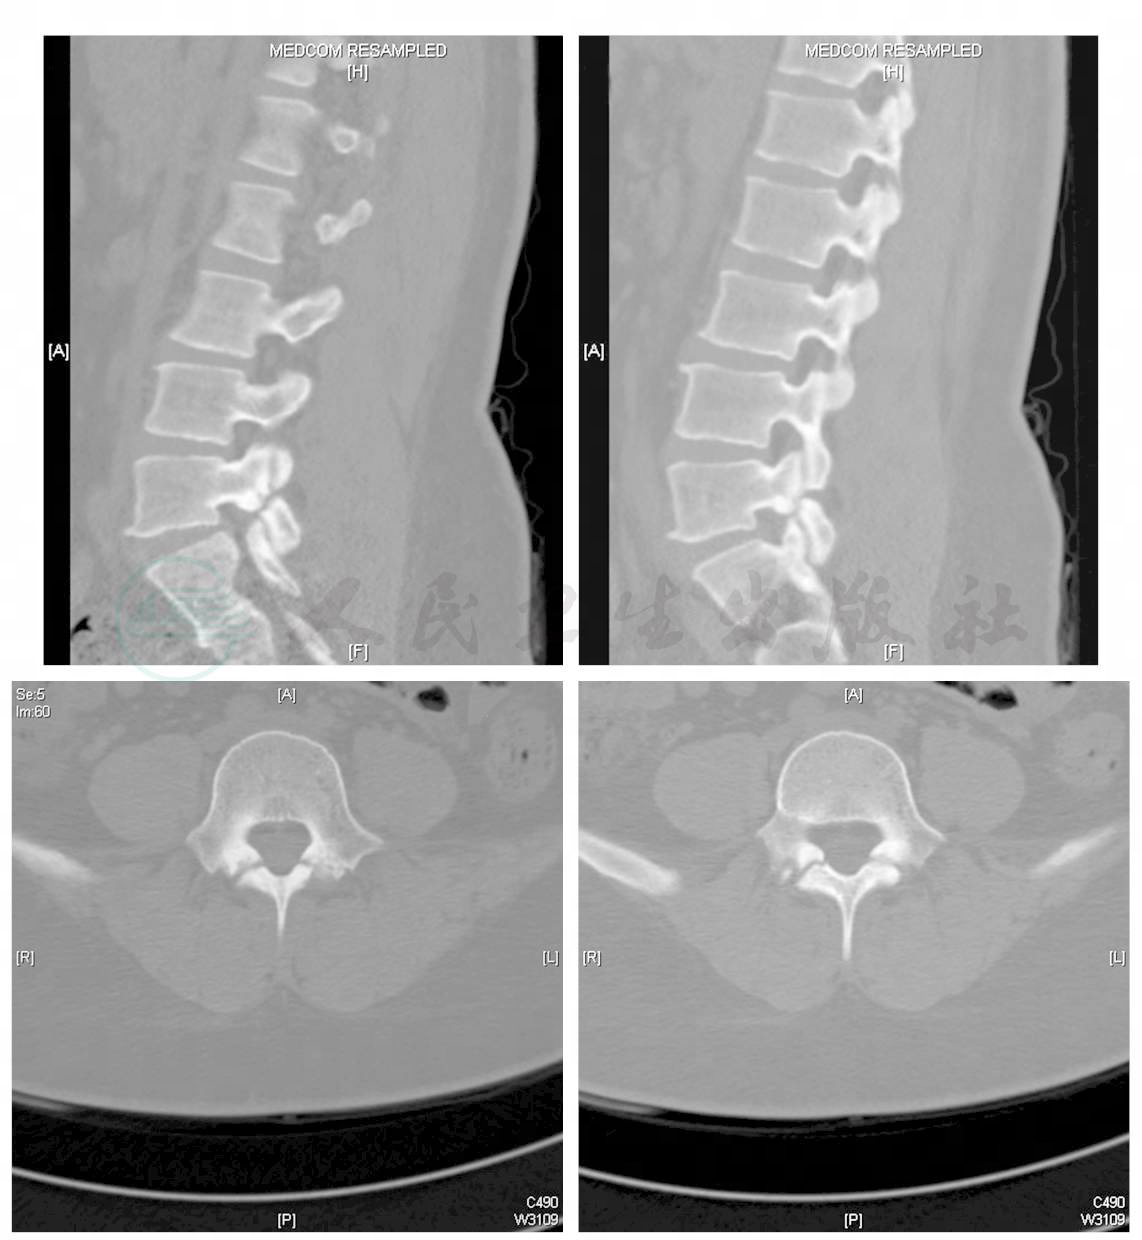

腰椎滑脱是一种常见的骨科疾病,指因椎体间连接异常发生的上位椎体于下位椎体表面部分或全部的滑移一腰椎滑脱的定义腰椎滑脱简单地说是指一个椎体在另一个椎体上向前或向后移位脊椎滑脱有5种类型,包括发育不良峡部裂退行性病变创伤性病变和病理性病变其中,退行性腰椎滑脱是最常见的类型。

腰椎滑脱是指因椎体间连接异常发生的上位椎体于下位椎体表面部分或全部的滑移简单来说,就是一个椎体在另一椎体上向前或向后移位,一般为前滑脱,后滑脱好发于腰5和腰4椎体以下是关于腰椎滑脱的详细解答一病因 先天性因素出生时即存在腰椎结构异常,如峡部不连等后天性因素包括各种过度的机械应力,如搬运重物举重外伤磨损和撕。

腰椎滑脱是指腰椎椎体序列变得不整齐,腰椎椎体可以向前或向后移位的一种神经外科常见病以下是关于腰椎滑脱的详细解释定义与表现腰椎滑脱通过侧位X线检查可以观察到,主要表现为腰椎椎体在序列上不再保持整齐,而是出现向前或向后的移位这种移位可能导致椎管狭窄,进而压迫神经,引发一系列临床症状,如。

腰椎滑脱症是指腰椎椎体间部分或全部错位的一种疾患,临床上一般称之为滑椎以下是关于腰椎滑脱症的详细解释定义与分类腰椎滑脱是指上位椎体相对于下位椎体向前或向后滑移根据病因,腰椎滑脱可分为真性滑脱和假性滑脱真性滑脱由腰椎峡部崩裂导致,假性滑脱则多与退行性改变有关发病原因退行性。

摘要腰椎滑脱,也称退变性腰椎滑脱,是由于先天性发育不良创伤劳损等原因造成相邻椎体骨性连接异常而发生的上位椎体与下位椎体部分或全部滑移腰椎滑脱多发生于5060岁的老年人,其症状有腰痛或腰腿痛等腰椎滑脱的治疗方法有手术治疗和非手术治疗两种下面一起来看看腰椎滑脱的病因症状治疗和预防等知识腰椎。

腰椎滑脱易于导致慢性腰痛以及一侧或双侧下肢的放射性麻木疼痛腰椎滑脱是指腰椎椎体间部分或全部错位的一种疾患,临床上一般称之为滑椎,一般是上位椎体向前滑脱腰椎滑脱的发病率在欧洲为3~7%,国内还缺乏准确的统计资料,一般认为,对有腰痛的患者的常规X摄片检查发现在成人中约5%患有腰椎滑脱的倾向。